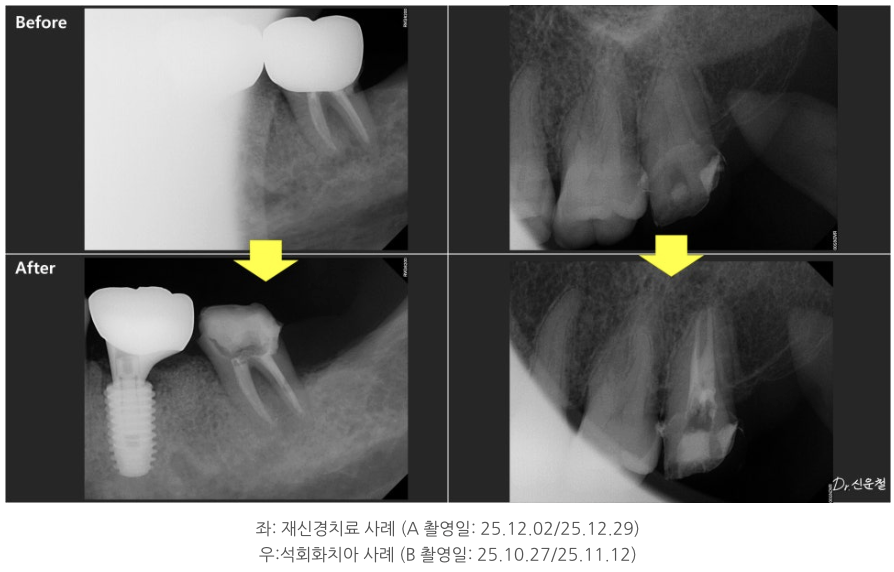

석회화된 치아, 정말 방법이 없을까?

실제 내원 사례 중에는

이미 신경치료를 받은 어금니에서

잇몸이 다시 붓고 고름이 차

발치 진단을 받고 오신 분도 계셨습니다.

또 다른 분은

“신경치료가 어렵다”는 설명을 듣고

의뢰로 내원하신 경우였습니다.

이 치아의 특징은 치아 안쪽 신경이 지나가는 길이

오랜 시간에 걸쳐 점점 막혀 있던 상태,

즉 석회화였습니다.

석회화란

원래 신경이 지나가야 할 공간이

시간이 지나면서 막히는 현상입니다.

방사선 사진에서 신경관이 잘 보이지 않거나

CT에서 신경이 있어야 할 자리가

빈 공간이 아닌 뼈처럼 보이는 경우가 이에 해당합니다.

겉으로 보면

“이제는 방법이 없는 치아”처럼 보일 수 있습니다.

중요한 건 ‘과거 치료’가 아니라 ‘지금 상태’

이 두 경우 모두에서

치료 시작 전 가장 중요했던 기준은

과거에 어떤 치료를 받았는지가 아니라,

- 지금 이 치아 안쪽에 다시 접근할 수 있는 여지가 있는지였습니다.

치아 안쪽을 직접 확인하면서

남아 있는 길이 있는지

다시 정리가 가능한 상태인지 를 기준으로 판단했고, 그 결과

두 경우 모두 발치 대신 신경치료를 진행할 수 있었습니다.